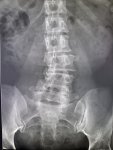

Здравствуй двачик, пишет вам простой рентгенолог из мухосранской поликлиники, сегодня я буду флексить зарплатой за ноябрь! Аж ПЯТЬДЕСЯТ ТРИ ТЫЩИ ПЕРЕВЕДУТ! С пруфом! А чего достигли вы? Ну и в доктора тож поиграем! Я буду вам картинки показывать, а вы пиздецомы находить! Найдите пиздецому на фтчк! Отчет еще по фог считать квартальный и годовой сегодня :-(